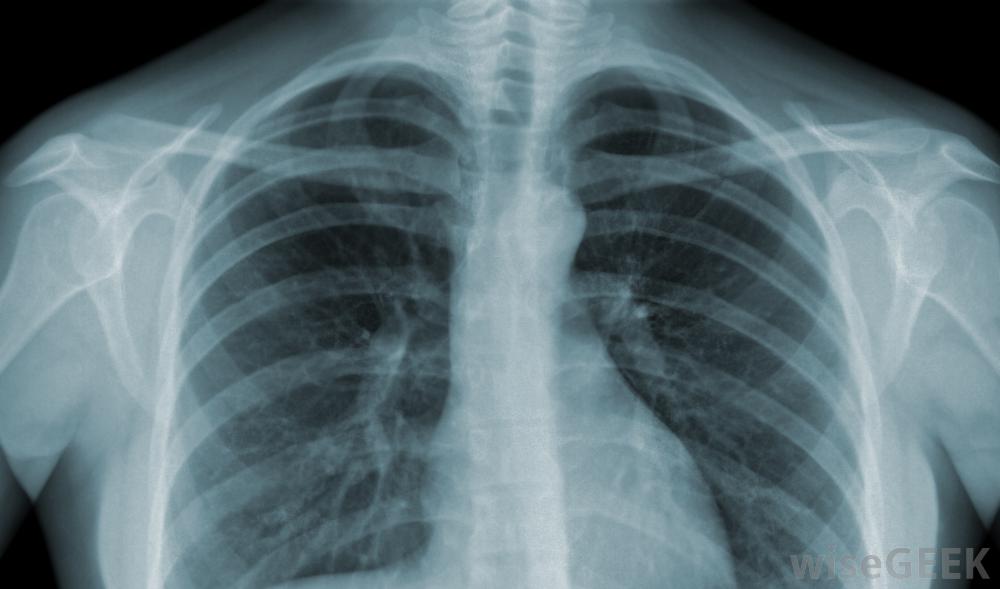

锁骨随时间的变化可通过X光片进行诊断。第一次记录的锁骨远端骨溶解损伤是在1936年。在本例中,一名空气锤操作员表现为肩部酸痛,没有明显的外伤。随着意识和竞技运动的普及,这些损伤的发生率增加。